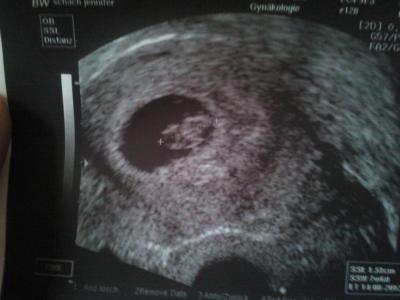

Ich war heute beim Frauenarzt und meinem Krümmel geht es gut, das Herzchen hat kräftig geschlagen:)) nur mein ET hat sich um 3 Tage nach hinen verschoben und deshalb bin ich jetzt nicht schon in der 9 Woche sondern noch Ende 8 Woche... hatte das jmd von euch auch? und wie findet ihr mein Bildchen? Liebe Grüße

Bild zu alles in Ordnung - Forum für August - Mamis

Wow wunderschönes Foto.....und dein Kümelchen ist sooooooo schön Gratuliere....... Mit dem verschieben, da kommt es darauf an wie sich dein Krümelchen entwickelt und auf die größe also ist das okay, nicht schlimmes einfach rein rechnerich verendert...... LG Jana

Ein sehr schönes Bild hast du da von deinem Schatz!!!! Liebe Grüße